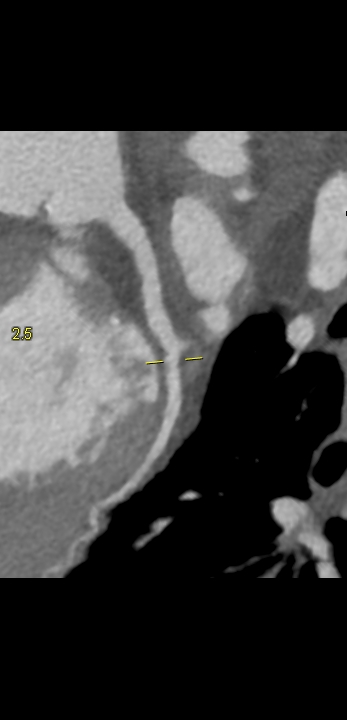

Figururile 1-9: reconstrucție în axul lung al vasului pentru arterele coronare cu evidențierea unui calibru global crescut la nivelul acestora și cu încărcătură ușoară-moderată de placă în principal calcificată

Discuţie caz nr 132: Examinările coroCT se efectuează în principal pentru aprecierea încărcăturii de placă precum și pentru evidențierea reducerilor de lumen ce necesită tratament. Această examinare a evidențiat creștere globală a calibrului arterelor coronare și o încărcătură ușoară-moderată cu placă în principal calcificată, fără a se evidenția arii de stenoză.

DE LUAT ACASĂ!!! Ectazia coronariană este o afecțiune rară caracterizată prin dilatarea anormală (diametrul vasului este de 1.5 ori mai mare) a arterelor coronare, care poate duce la afectarea fluxului sanguin și la un risc crescut de ischemie. Etiologia nu este cunoscută iar afecțiunea poate fi asociată cu ateroscleroză sau factori congenitali și reprezintă o provocare atât în diagnostic, cât și în tratament. Simptomele se suprapun adesea cu cele ale altor boli coronariene, ceea ce face ca identificarea timpurie să fie crucială. Opțiunile de tratament variază de la tratamentul medical cu terapie antiplachetară sau anticoagulantă până la proceduri intervenționale, cum ar fi angioplastia sau intervenția chirurgicală, în funcție de severitatea și riscul de complicații. Tratamentul pe termen lung se concentrează pe prevenirea evenimentelor ischemice și pe abordarea cauzelor care stau la baza acestora.